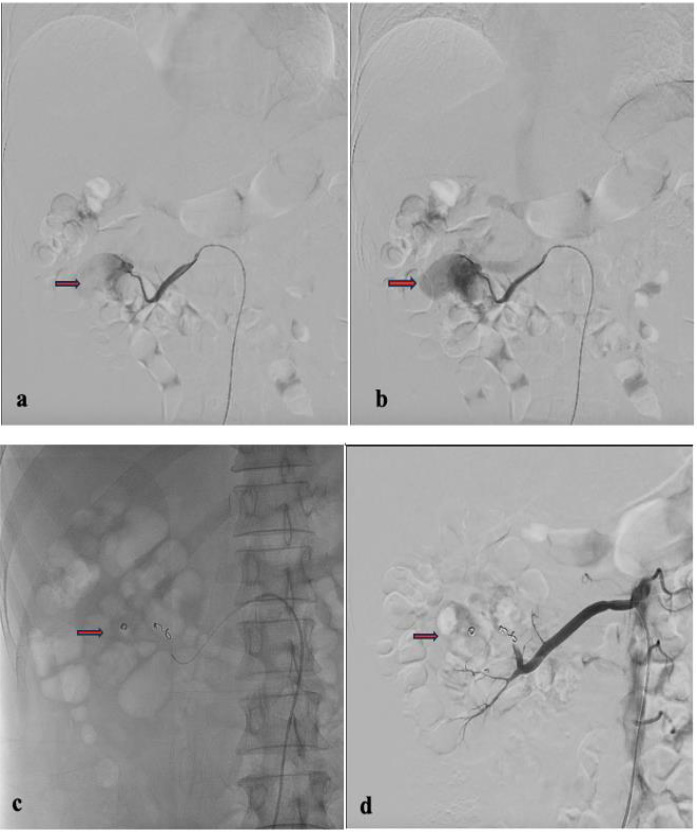

Fig. (4).

Second angiography with a cobra catheter and microcatheter. (a) Coil post first embolization procedure; (b) Pseudoaneurysm of the right renal upper pole segmental artery; (c) Super selective embolization; (d) A contrast test was performed, and the right renal segmental artery was seen to be significantly embolized.

A contrast test was performed that revealed the presence of another pseudoaneurysm. The right renal segmental artery, located in the upper pole of the right kidney, appeared to be the source of the pseudoaneurysm, which the first embolization failed to find or treat. We used 4 mm and 5 mm Coiling Vortx 18 pushable and a PVA 500-710 to target the right renal segmental artery branch and the upper pole of the right kidney. We performed a contrast test and observed significant embolization of the right renal segmental artery, which ultimately resolved the hematuria (Fig. 4). After receiving treatment, the patient's complaints decreased, and hematuria no longer occurred.